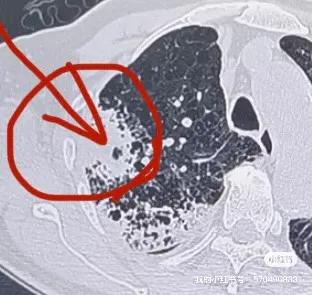

一個78歲合併冠狀動脈重度狹窄的冠心病病人,體檢發現右肺腫塊,由於不敢手術與常規穿刺活檢,在當地三甲醫院花了14800元做了血液基因檢測未發現相關驅動基因突變,準備做區域性放療,但又沒有病理診斷,最後多方打聽最終選擇一種國內特色的肺穿刺活檢技術——氬氦刀冷凍隧道式肺活檢專利技術。在局麻CT引導進行了冷凍活檢手術,活檢多條大塊組織標本,術中冰凍病理診斷是腺癌,即刻同期進行區域性完全性氬氦刀冷凍消融手術。其餘標本再次進行組織基因檢測,發現是EGFR21突變。後續直介面服奧希替尼靶向藥物治療,5個月後,腫瘤完全消失,腫大的縱隔淋巴結也恢復正常,臨床評估CR。本案例說明:1.對於不能手術、合併複雜基礎疾病或高齡的肺腫塊病人,這種特色是肺穿刺活檢技術(冷凍隧道活檢技術+穿刺標本現場冰凍病理診斷技術+同期冷凍消融技術)就是一種很好的選擇;2.對於腫瘤基因檢測,本案例顯示血液標本的準確性低於組織標本;3.對於腫瘤診療,只有精準診斷才有精準治療。